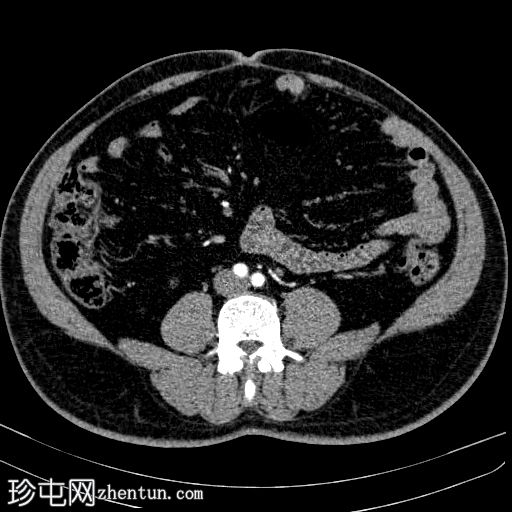

轴位

平扫

在左侧输尿管膀胱连接处可见一枚24×15 mm的大膀胱结石。膀胱壁轻度弥漫性增厚,厚度约6 mm,提示膀胱炎。

左肾上极发现一单纯性皮质囊肿,Bosniak I 型,大小为 13 mm。

可见多个副脾(脾小体),位于主脾实质的上方和下方,在影像学各期均表现出与脾脏相似的衰减值。

肝脏弥漫性脂肪浸润。